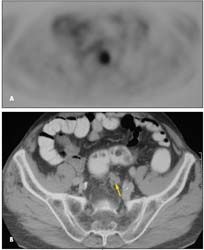

. One PET image shows a lesion in the inferior aspect of the medial segment of the left lobe of the liver, which is also visible on the corresponding CT image (

Figure 1

).

Another PET image reveals a lesion within the dome of the liver in the most superior aspect of the anterior segment of the right lobe; this lesion is not seen on the corresponding CT image (

Figure 2

A third PET image shows adenopathy in the superior aspect of the pelvis posteriorly, which is consistent with extrahepatic metastatic disease; no adenopathy was appreciated at first in the corresponding CT image; however, it was identified retrospectively (

Figure 3